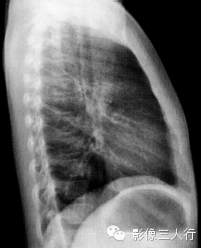

报告示范:双肺肺纹理增强,左肺门影增大。胸廓对称,纵隔、气管居中。心脏形态、大小、位置正常。双侧膈肌光滑,肋膈角锐利(图2)。

图2胸内淋巴结结核(男患,8岁,咳嗽半个月)

(B)侧位